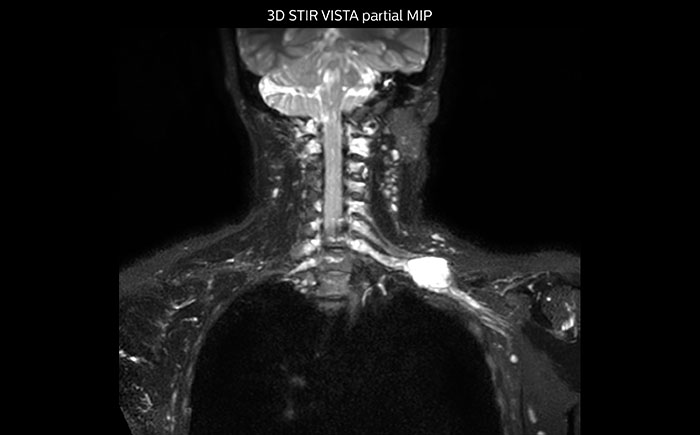

Hier handelt es sich um eine 43-jährige Patientin mit einem supraklavikulären Nervenscheidentumor links. Die Läsion ist auf den STIR VISTA Bildern und auf der MR-Neurographie mit diffusionsgewichteter MRT gut zu erkennen. Die Untersuchung wurde mit Prodiva 1.5T durchgeführt.

Erfasste Voxelgröße: 1,2 x 1,3 x 2,4 mm, rekonstruierte Voxelgröße: 0,7 x 0,7 x 1,2 mm, dS SENSE Faktor: 2, Scandauer: 5:46 Minuten.